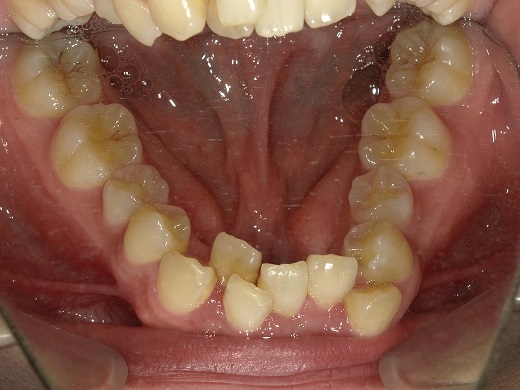

治療前上顎

治療後下顎